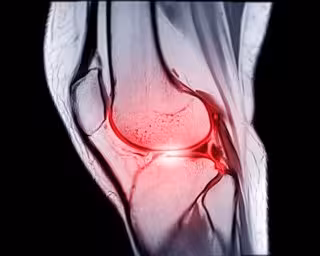

Archivo - Imágenes por resonancia magnética o resonancia magnética de rodilla sagital PDW y TIW vista para detectar el desgarro o esguince del ligamento cruzado anterior (LCA).

Archivo - Imágenes por resonancia magnética o resonancia magnética de rodilla sagital PDW y TIW vista para detectar el desgarro o esguince del ligamento cruzado anterior (LCA). - MR.SUPHACHAI PRASERDUMRONGCHAI/ ISTOCK - Archivo